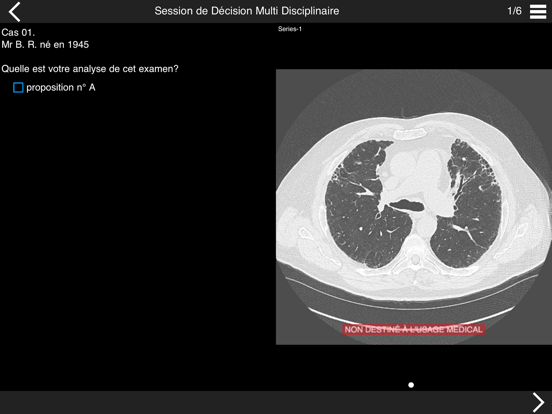

Consultez les examens tomodensitométriques des cas cliniques de pneumopathie infiltrante présentés lors de la session de discussion multidisciplinaire qui aura lieu dans la première partie de l'après-midi.